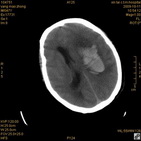

病人杨XX,男,青云街道办事处路踏泉村,住院号51666,CT号:104770。病人因“高血压脑出血”在新泰市人民医院住院治疗5天,治疗效果不佳转入我院,复查CT示左基底节血肿,病人昏迷状态,给予血肿清除术,术后2天复查CT,血肿完全清除,病人恢复好,治疗效果满意。附病人术前术后CT片资料如下。

术前CT

术前CT1 术前CT2 术前CT3 术前CT4